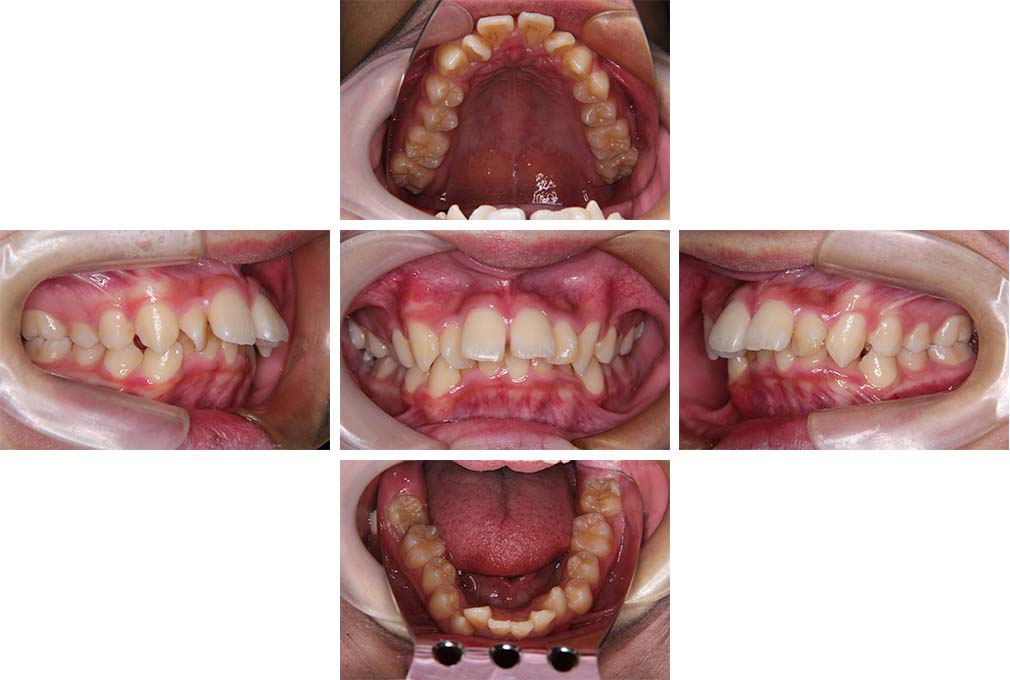

CASE:04

アングルⅢ級傾向を持つ叢生

初診時年齢 22歳

性別 女性

治療費の目安 105万円程度(治療開始時)

上顎右側犬歯が唇側に転位していることを主訴に県内歯科医院から紹介来院された。骨格的にはⅢ級傾向で上顎右側犬歯が唇側転位となり、側切歯が口蓋側に転位していた。下顎前歯が叢生になっていることも相まって上下の正中線は右側に大きくずれていた。アングルⅢ級傾向を持つ上下顎前歯部叢生と診断した。

上下顎小臼歯を抜歯していただき上顎舌側、下顎唇側マルチブラケット装置を使用して動的治療を行った。矯正用ゴムの使用など協力状態も良く、正中線の大きな移動があったのも関わらず2年10カ月で装置を撤去し保定へ移行した。保定移行後14年が経過し、ご息女の診察でご来院いただいていたことから、口腔内を拝見したが、下顎前歯のわずかなずれがあったものの大きな歯列の乱れはなく歯列は安定していた。動的治療期間2年10カ月間。

治療前

22歳6か月

治療後

動的治療期間2年10カ月間

25歳6か月

治療終了

動的治療終了後2年2カ月

28歳8か月

14年経過

動的治療終了後14年7カ月

40歳1か月